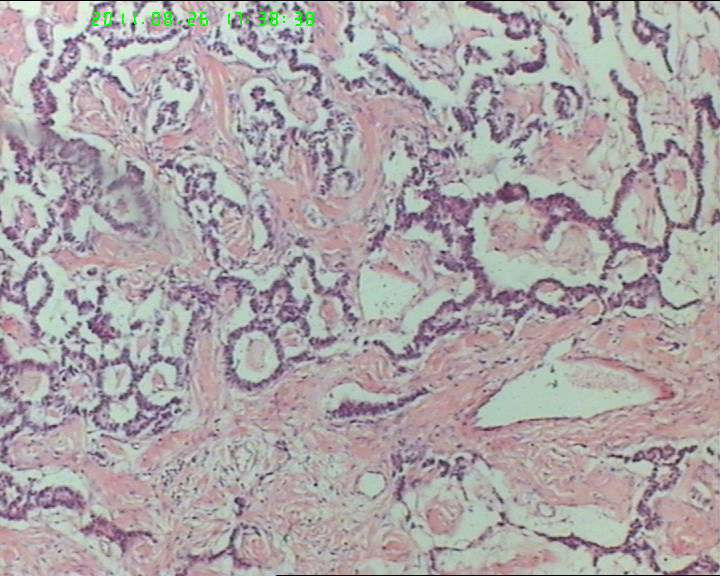

76岁女性卵巢巨大囊性肿物

卵巢肿物,大小18*14*10cm

,切面灰黄色,中央见一囊腔,12*4cm大小,未见内容物,内壁光滑。囊壁厚约4cm。

本例瘤细胞虽排列呈菊形团或腺管样,但瘤细胞核内未见核沟,核的形态也不是典型的石榴子样,故颗粒细胞瘤是个排除性诊断,本例还有一个特点是瘤细胞团周围有一收缩裂隙,提示其最有可能是类癌,唯一不足的是未见丰富的血窦

图7的两种不同分化上皮之间是个什么关系?移行还是共存?

卵巢类癌还是比较少见的,以前赵老师发的一个性索间质肿瘤的组织学变型中,好像有类似的图